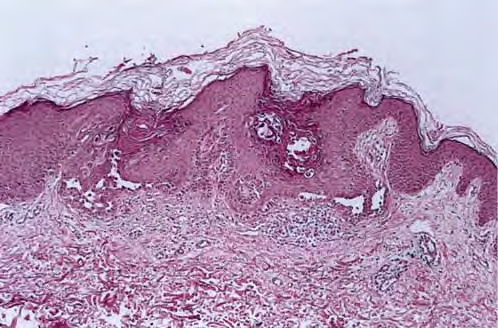

The characteristic changes in Darier’s disease include the following: (a) a peculiar form of dyskeratosis resulting in the formation of corps ronds and grains; (b) suprabasal acantholysis leading to the formation of suprabasal clefts or lacunae; and (c) irregular upward proliferation into the lacunae of papillae lined with a single layer of basal cells, so-called villi (Fig. 6-27). There are also papillomatosis, acanthosis, and hyperkeratosis. The dermis shows a chronic inflammatory infiltrate. In some cases, there is downward proliferation of epidermal cells into the dermis.

The corps ronds occur in the upper stratum malpighii, particularly in the granular and horny layers; grains are found in the horny layer and as acantholytic cells within the lacunae. Corps ronds possess a central homogeneous, basophilic,

pyknotic nucleus that is surrounded by a clear halo. By virtue of size and the conspicuous halo, corps ronds stand out clearly . Peripheral to the halo lies basophilic dyskeratotic material as a shell . The nonstaining halo in some instances is partially replaced by homogeneous, eosinophilic dyskeratotic material . Compared with the corps ronds, the grains are much less conspicuous. They resemble parakeratotic cells but are somewhat larger. The nuclei of grains are elongated and often grain shaped and are surrounded by homogeneous dyskeratotic material that usually stains basophilic but may stain eosinophilic. The lacunae represent small, slitlike intraepidermal vesicles most commonly located directly above the basal layer. They contain acantholytic cells and show premature partial keratinization. Because of shrinkage, some of them are elongated, and these then appear identical with the grains in the horny layer. The villi projecting into the lacunae may be quite tortuous, so on histologic examination, some of them appear in cross section as rounded dermal structures lined by a solitary row of basal cells .